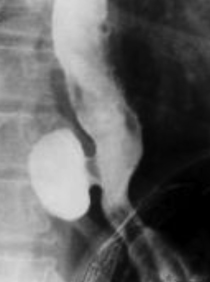

Image TOGD d'une megaoesophage sur

le cliche de face et OAD . Bord lisse et

aperistaltisme ., la retressisement a inferieure est

image en queue de radis |

Megaoesophage en face

et en profile OAD |